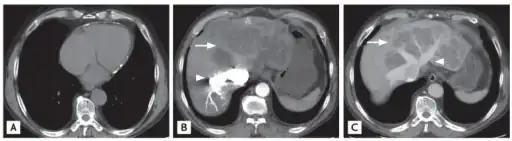

a) Sparse pericardial calcification with eccentric wall thickening b,c) liver CT shows variable regions of low attenuation, often called the “nutmeg liver” arrows

CT appearance of liver in congestive hepatopathy, sometimes referred to as a nutmeg liver. Due to congestion, contrast does not flow through the liver in a normal manner. Axial and coronal images in the portal venous phase.